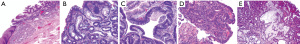

The process of developing BE is said to occur in two steps. The first step occurs secondary to the reflux of both gastric fluid and duodenal secretions onto the squamous epithelium of the esophagus which transforms it into simple columnar epithelium, that of the cardiac mucosa. This chronic mucosal injury occurs over a span of a few years and involves an inflammatory cascade that stimulates cellular proliferation and genetic alterations that then induces genetic destabilization. The second step spans over 5 to 10 years and involves intestinal metaplasia via the development of goblet cells (Figure 1). Once BE is present, the development of low-grade dysplasia (LGD) to high-grade dysplasia (HGD) and eventually adenocarcinoma occurs through the metaplasia-dysplasia-carcinoma sequence (Figure 2). Alterations of architecture and cytologic processes differentiate LGD from HGD (16). Notwithstanding this increased cancer risk, the annual rate of progression of BE to EAC is 0.1% to 0.5% and the rate of progression of HGD to EAC is 6% (17).